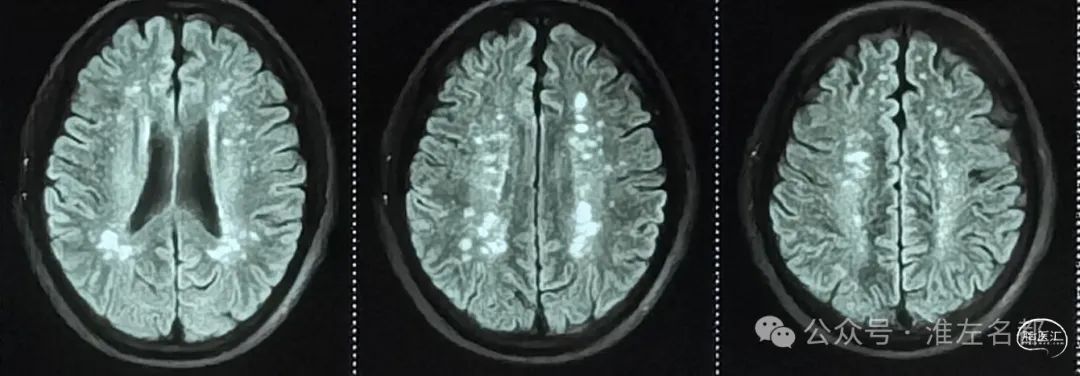

FLAIR👆🏻

T2WI和FLAIR:左侧脑桥内部腔隙性梗死灶高信号。

FLAIR:双侧侧脑室旁和皮质下多发脑白质改变(慢性缺血所致)。